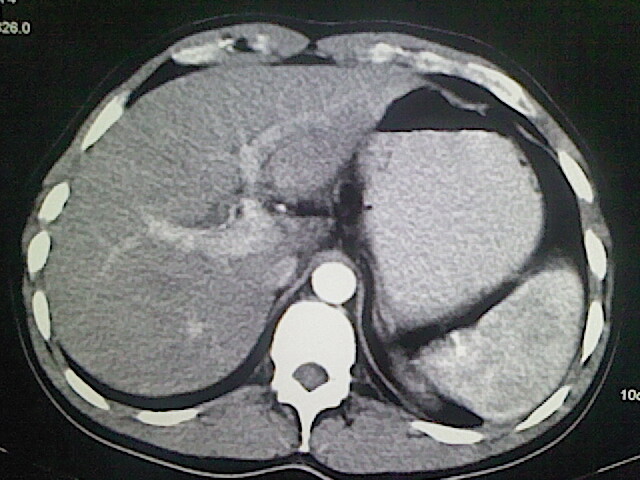

以下是引用卜一在2009-3-14 9:49:00的发言:[br]胆囊萎缩,胆囊壁不规则增厚,内部结构模糊,增强明显强化。另:肝左叶外侧段肝囊肿。支持:慢性胆囊炎!高度可疑:胆囊癌!

以下是引用余辉在2009-3-14 8:48:00的发言:[br]1)慢性胆囊炎。2)肝左叶外侧段肝囊肿。3)脂肪肝。[br]支持,胆囊萎缩,密度增高,不知b超具体有何提示,钙胆汁?结石?

以下是引用jiangjing在2009-3-14 10:18:00的发言:[br]1)慢性胆囊炎。2)肝左叶外侧段肝囊肿。3)脂肪肝。4.】建议行肝功能检查